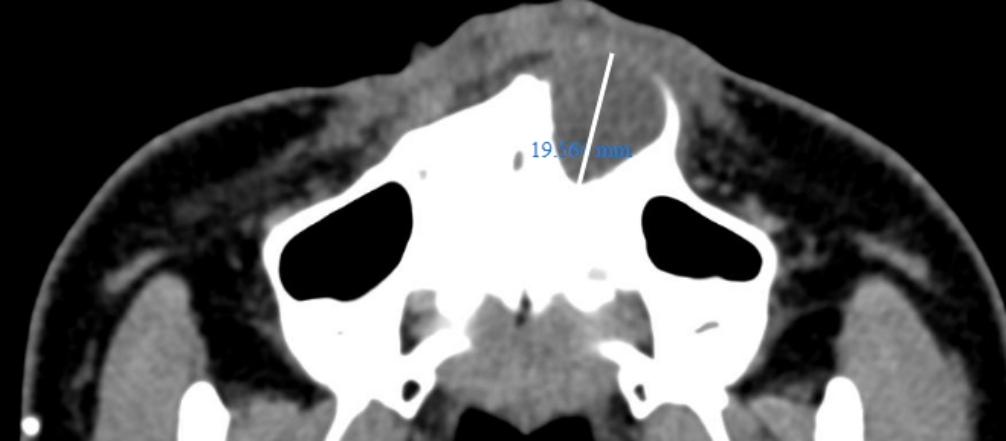

接下来的进一步检查印证了医生的推论。CT检查显示,陈女士这颗门牙根尖处,长了一个直径19.56mm大小的囊肿,侵及了旁边的侧切牙,牙槽骨外表面的骨壁已被压迫吸收。